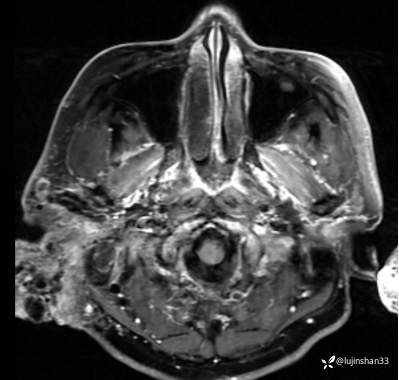

(2023-02-17 17:52,本院)行CT(血管心脏)检查提示:1、右侧耳颞部异常改变,考虑血管瘤可能,可见粗大供血动脉及引流静脉,局部动静脉瘘可能,右侧颈外动脉分支增粗,请结合临床及相关检查。2、左侧颈内动脉粥样硬化,管腔轻微狭窄,请结合临床。血管外科会诊意见:CTA示右颈外动脉起始部结扎后闭塞,介入栓塞暂无合适入路;

临床诊断:耳廓、颞骨蔓状血管瘤合并出血